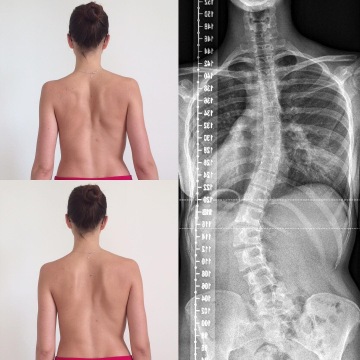

(ilustrační foto od lektorky)